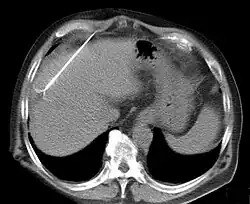

Die am Markt verfügbaren Geräte haben je nach Hersteller unterschiedliche Bauart mit dem Ziel, eine möglichst große und dabei kontrollierte Nekrosezone zu erzeugen. RITA/Angiodynamics verwendet dünne Aufspreizelektroden und einen 460 kHz-Generator, der 250 Watt leistet.[2] Radionics verwendet stabförmige, gekühlte Elektroden und gepulste 480-kHz-Wellen, bei max. 200 Watt Leistung. Vor- und Nachteile der Systeme halten sich bisher die Waage. Pro Elektrodenposition können ca. 2,4-2,8 cm große Gewebeareale zerstört werden. Dabei fließt ca. 1 Ampere Strom. Nach 12 bis 20 Minuten verkohlt das unmittelbar an der Elektrode gelegene Gewebe unter Gasbildung; damit steigen elektrischer Widerstand und Impedanz an, und die Energieübertragung kommt zum Erliegen. Zur Lagekontrolle der Sonden dient Sonografie oder Computertomographie.[3]

In der Behandlung von Lebermetastasen (Tumorabsiedlungen in der Leber) wird die Hochfrequenzablation zunehmend als Alternative zur Leberteilentfernung verwendet. Vorteile der Hochfrequenzablation sind:

- Minimalinvasive Anwendung möglich: Die Behandlung kann häufig durch Punktion durch die Haut (also ohne Operation) angewendet werden

- Gewebesparend: Aufgrund anatomischer Gegebenheiten muss bei einer Operation von Lebermetastasen häufig ein Teil der Leber entfernt werden, der wesentlich größer ist als die Metastase. Bei der Hochfrequenzablation wird nur die Metastase selbst mit einem Sicherheitsabstand von 10 mm zerstört.

Derzeit existiert keine größere prospektiv randomisierte Studie zum Vergleich der Hochfrequenzablation mit der Resektion von Lebermetastasen. Der direkte Nachweis der krebstherapeutischen Sicherheit der Methode ist also nicht erbracht. Allerdings deuten die bislang verfügbaren Daten auf eine Gleichwertigkeit dieser Therapieformen bezüglich der krebstherapeutischen Sicherheit hin.